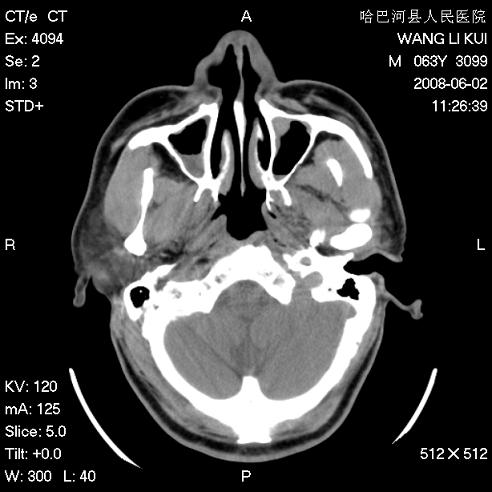

标题: CT13803:反复性鼻塞、流涕一年余 [打印本页]

标题: CT13803:反复性鼻塞、流涕一年余

副鼻窦炎,右上额窦积脓。左眼肌锥内见致密影,视神經受压

1.全组副鼻窦炎2.双侧上颌窦积液

1)全副鼻窦炎(左侧上颌窦黏膜下囊肿或息肉)。2)左眼眶肌锥内不规则小结节状软组织密度影;考虑为小血管瘤可能。建议行ct增强扫描检查。

全组副鼻窦炎,左侧肌锥内不规则形软组织肿块影,与眼外肌密度相当,左侧视神经受压,肿块与视神经及眼外肌分界清晰,眼外肌无增粗,眶壁无破坏,球后脂肪间隙不模糊,考虑良性改变,小血管瘤或神经源性肿瘤可能,建议增强扫描。

谢谢,增强扫描做了,眶内病灶与海绵窦同步明显强化,血管瘤